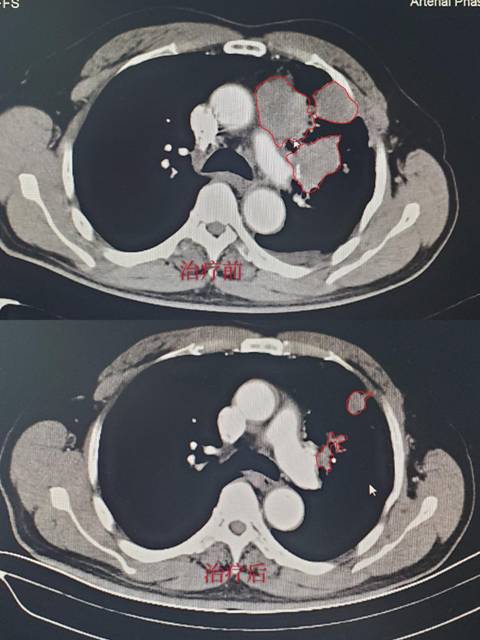

病例1:储某某,诊断为:左肺小细胞癌广泛期。经2周期治疗后复查胸部CT,肿瘤缩小达90%,肿瘤接近消失,达到很好的效果;(CT结果如下,红色线框内为肿瘤组织。)